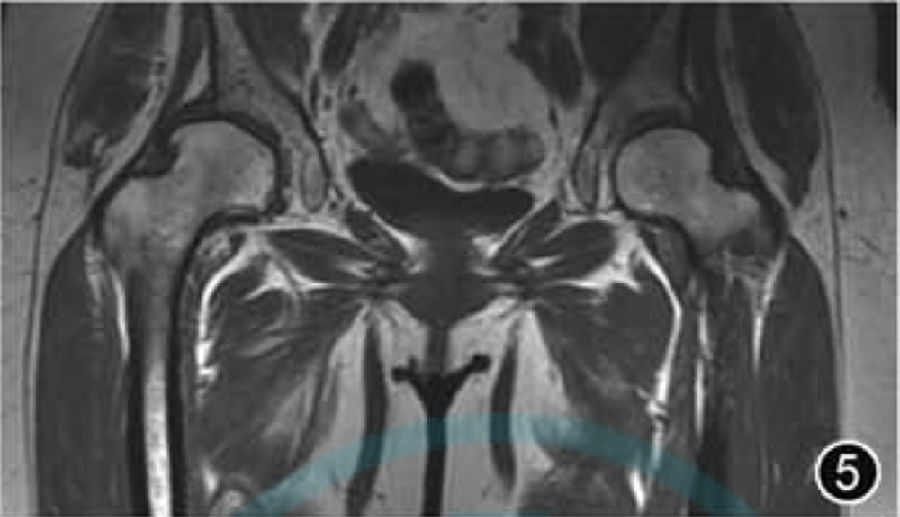

4.DDH:DDH是一种涉及股骨头和髋臼异常发育的疾病(图5),主要是由于髋臼相对较浅,导致股骨头覆盖不足,进而导致关节应力分布异常、关节不稳定、软骨损伤和继发性髋关节OA。放射科医师应熟悉婴幼儿髋臼骨、软骨、韧带和软组织结构,在使用MRI评估DDH时,应评估发育不良髋臼的后倾和股骨头覆盖程度,股骨头的延迟骨化可以通过双髋对比进行评估。MRI的主要优点是能够可视化软骨髋臼并确定其对股骨头的覆盖程度,比X线平片显示髋臼覆盖更准确。因为股骨头的中心在幼儿中较难确定,在MRI上可应用骨髋臼指数和软骨髋臼指数来评估DDH。需要注意的是,轻度DDH 时,角度测量结果可不提及。

图5 髋关节发育不良MRI图像。冠状面T1WI示髋臼与股骨头关节面对位不良,右侧髋臼对股骨头覆盖率明显降低